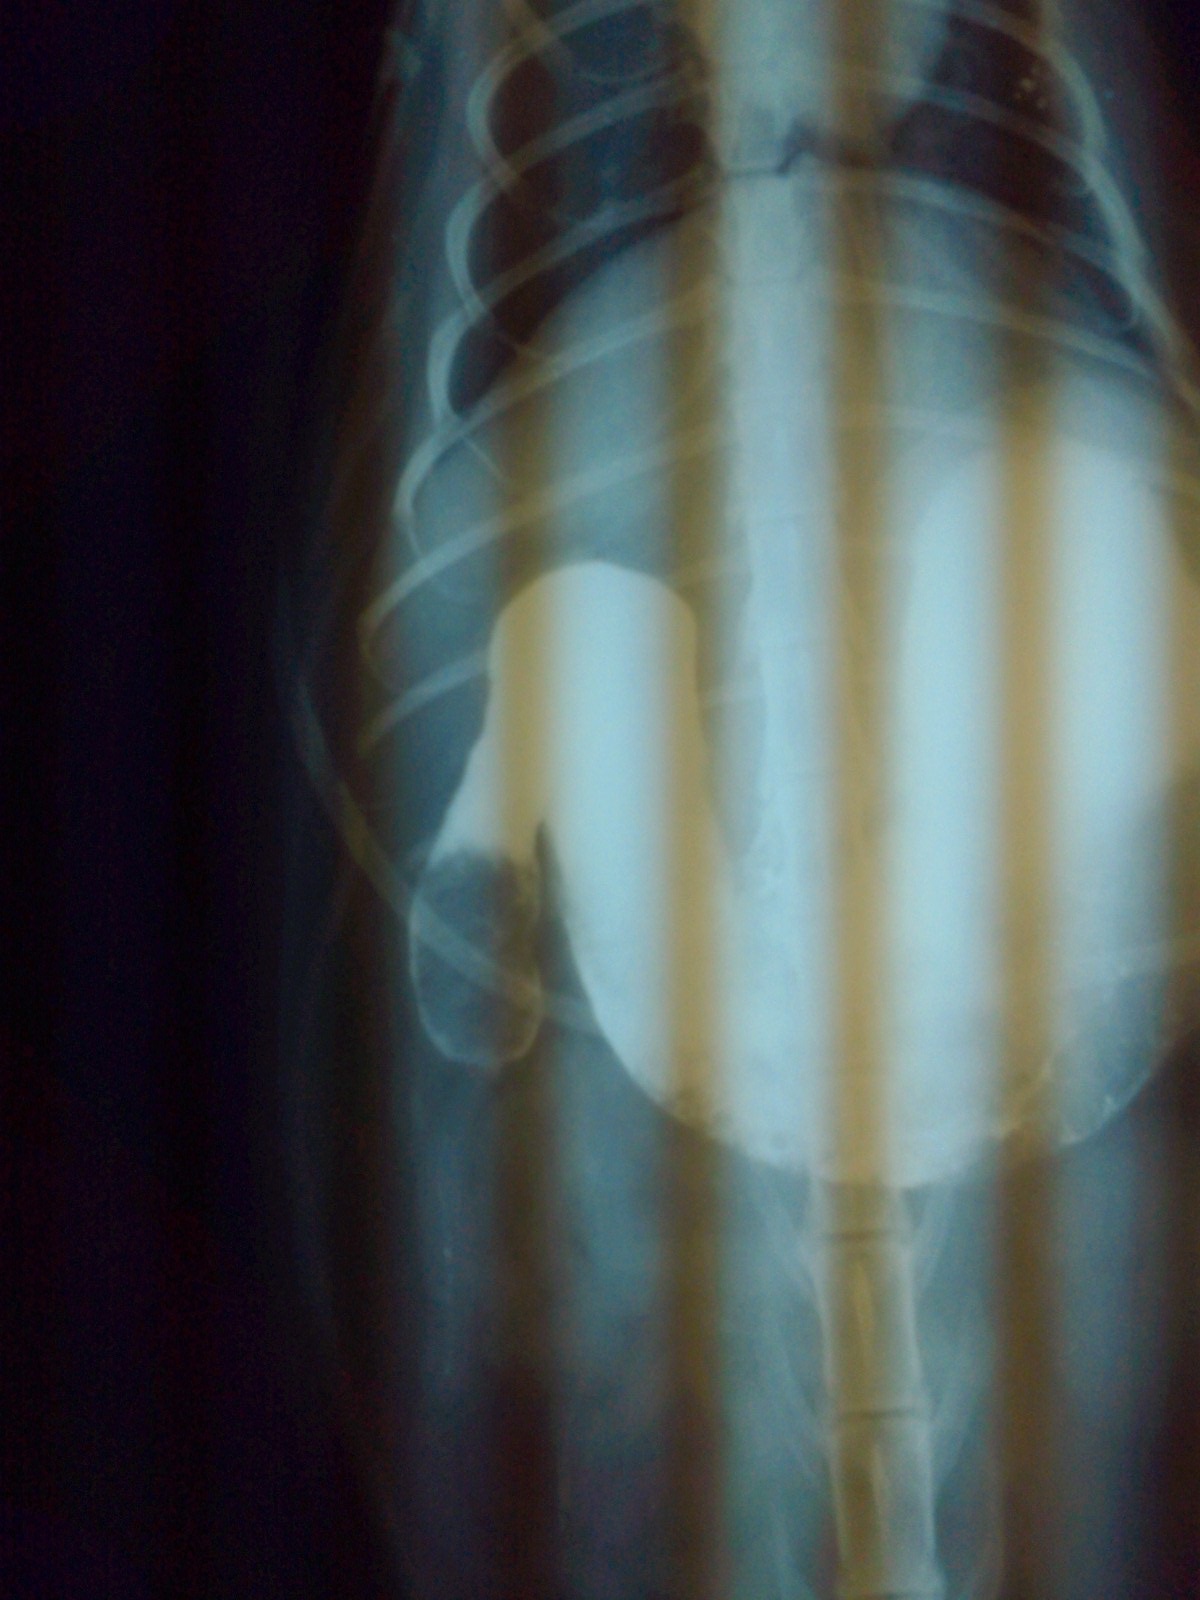

今日、状態がよくなったのでバリウムを飲ませて胃のレントゲンを撮ってみると、時間が経過してもバリウムが腸に降りていく気配なし。

それ以前に、こんなに大きな胃になっていることが変なのですが。真ん中の三角おにぎりのが胃。

で、だんだん見えてきたのが十二指腸あたりに楕円形の異物があり、それより先にバリウムが流れて行かない。これはマズイということで、急遽、手術して取り出すことなりました。